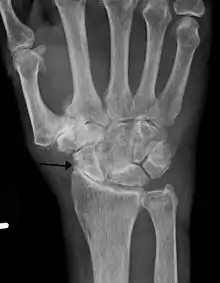

Diagnosis is made with reasonable certainty based on history and clinical examination.[42][43] X-rays may confirm the diagnosis. The typical changes seen on X-ray include: joint space narrowing, subchondral sclerosis (increased bone formation around the joint), subchondral cyst formation, and osteophytes.[44] Plain films may not correlate with the findings on physical examination or with the degree of pain.[45] Usually other imaging techniques are not necessary to clinically diagnose osteoarthritis.

Severe osteoarthritis and osteopenia of the carpal joint and 1st carpometacarpal joint.

Primary osteoarthritis of the left knee. Note the osteophytes, narrowing of the joint space (arrow), and increased subchondral bone density (arrow).